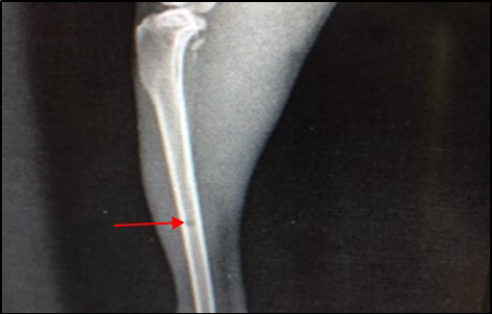

Site of operation, 7 days post treatment with Ceftaroline given intramuscularly (group D): A) Chronic Osteomyelitis (Seqeustrum still exists) (→) (ML View); B) Radiopaque area in soft tissue present represent accumulated pus (→) (AP View)